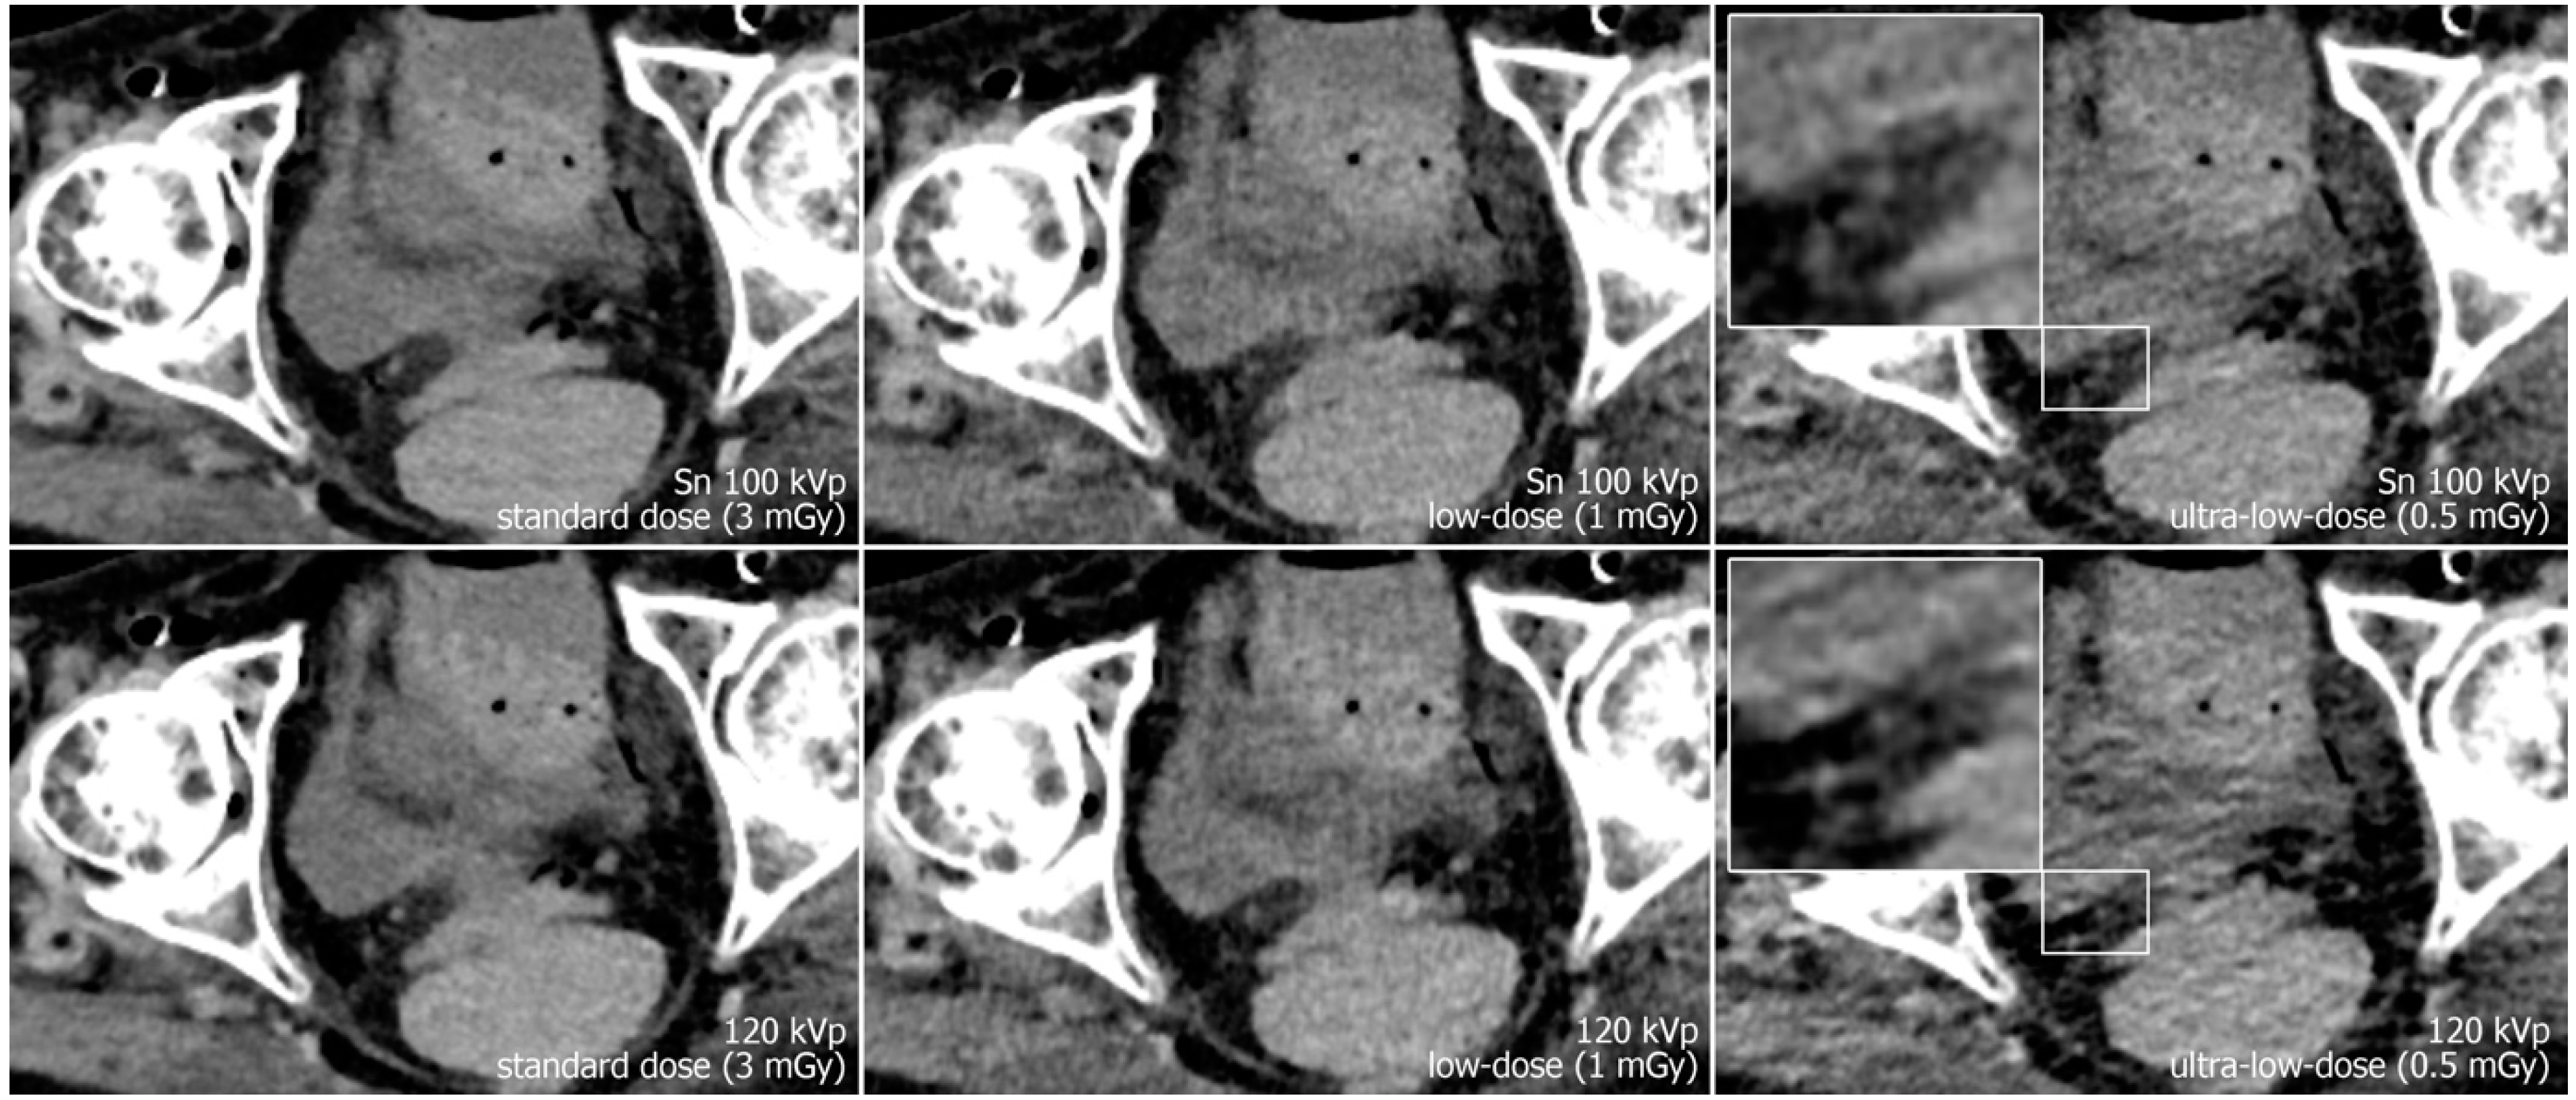

Reconstruction of datasets followed identical parameters: slice thickness and increment were set to 3 mm each, and the field of view to 400 mm with a 512 × 512 pixel matrix. A soft tissue convolution kernel (Br36) was applied with the highest strength level of a dedicated quantum iterative reconstruction algorithm (QIR 4). For polychromatic scans, “T3D” mode was enabled, which includes photon energies between 20 and 120 keV [29]. Window settings were pre-set to 300/40 Hounsfield units (width/center) were employed for dedicated analysis of soft tissue. However, readers were given the possibility to adjust these settings at will during image quality assessment. Examples regarding differences in image quality of the pelvic region between acquisition protocols are provided in Figure 1, while Figure 2 illustrates the encumbered demarcability of the lower Ureter in ultra-low-dose scans.

Figure 2.

Axial view of the right distal ureter (magnification) in a different specimen. Again, the image quality is reduced and demarcability of the ureter is impaired, especially in ultra-low-dose polychromatic imaging compared to the dose-matched protocol with tin filtration.